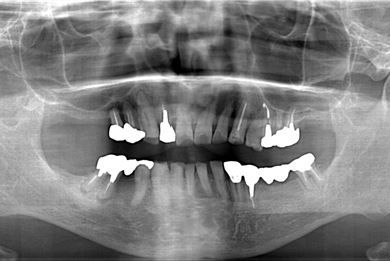

インプラントの症例写真 IMPLANT

骨再生インプラント治療+セラミック治療

| 性別/年齢 | 男性 / 60歳 | ||||||||||||||||||||||||||||||||

| 主訴 | 右上奥歯が動いて痛みがある。 | ||||||||||||||||||||||||||||||||

| 治療方針 | サイナスリフトにて上顎洞を拳上し、骨再生療法を用いてインプラント治療を可能にする。 | ||||||||||||||||||||||||||||||||

| 治療内容 | インプラント5本(サイナスリフト、GBR)、ハイブリッドセラミッククラウン5本、メタルボンドセラミッククラウン1本(メタルボンド用土台1本)、ハイブリッドセラミックインレー、遊離歯肉移植手術 | ||||||||||||||||||||||||||||||||